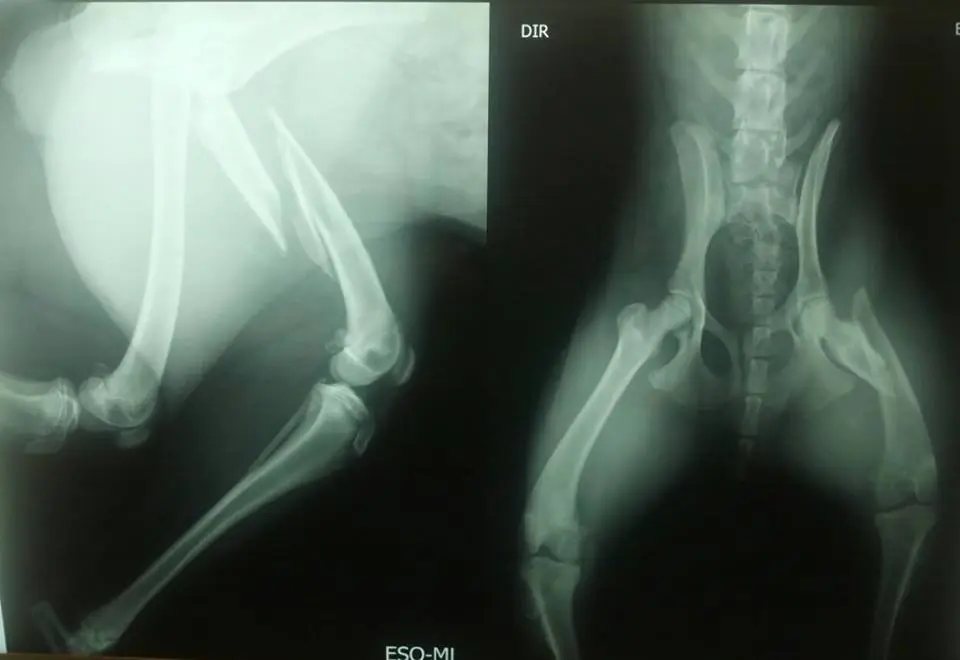

Esse é o RX da Sophia (Foto: Divulgação)

A cadela batizada de Sophia, uma SRD de porte médio, que tem no máximo 10 meses de vida, vivia em situação de abandono nas ruas de Sorocaba (SP) onde foi atropelada por alguém que não lhe prestou socorro. O acidente causou uma fratura na pata traseira.